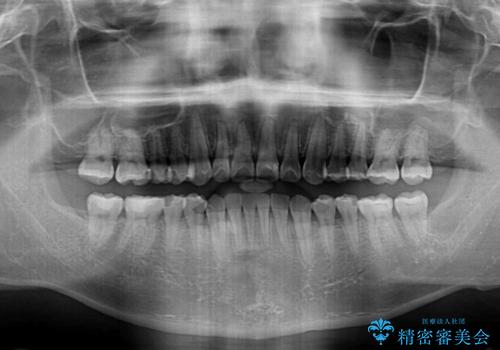

ディープバイトと叢生を解消 インビザライン矯正

- 前歯のデコボコを強い咬みしめを気にして来院された患者様です。

インビザラインを用いて、前歯の叢生を解消するとともに、ディープバイトを改善していくこととしました。

ディープバイトが改善されたことで、顎への負担が軽減され、更には上顎前歯の突出感も改善することができました。

矯正治療後には欠けてしまった修復物をセラミックインレーにて修復治療しました。